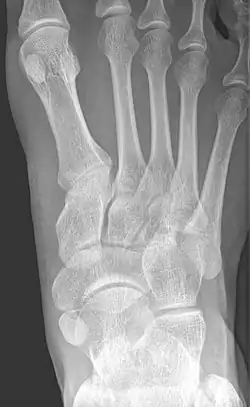

Radiological images

Type 2